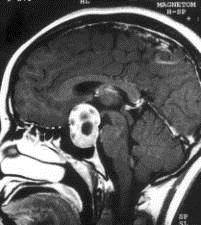

病历摘要:??患者男性,35岁。性功能减退2年,视力下降6月。既往体健。体检:神清,皮肤细腻,毛发稀疏。视力左眼0.3,右眼0.5,双瞳等大等圆,直径3....

问题 病历摘要:??患者男性,35岁。性功能减退2年,视力下降6月。既往体健。体检:神清,皮肤细腻,毛发稀疏。视力左眼0.3,右眼0.5,双瞳等大等圆,直径3.5mm,对光反射稍迟钝,双颞侧偏盲,双眼底视神经乳头原发性萎缩,余神经系统未见异常。 术前的准备应包括下列哪些?提示:拟经蝶窦入路手术治疗